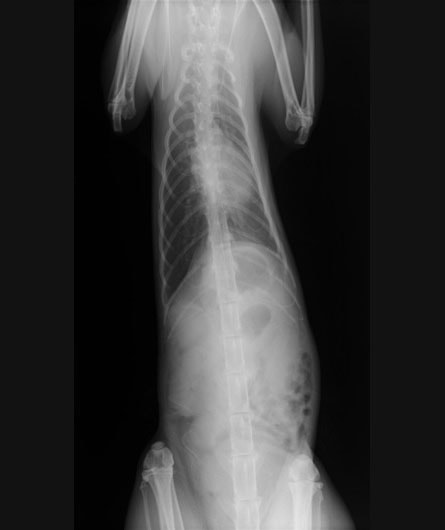

■ 症例:10歳 ドーベルマン 主訴:突然の嘔吐、虚脱

術前のレントゲン

身体検査上、鼓腸を伴う腹囲膨満、口腔粘膜の蒼白などが認められます。確定するには、レントゲン検査の実施が重要となります。その際、著しく拡張した胃が確認され、特徴的な捻転ラインが認められます。